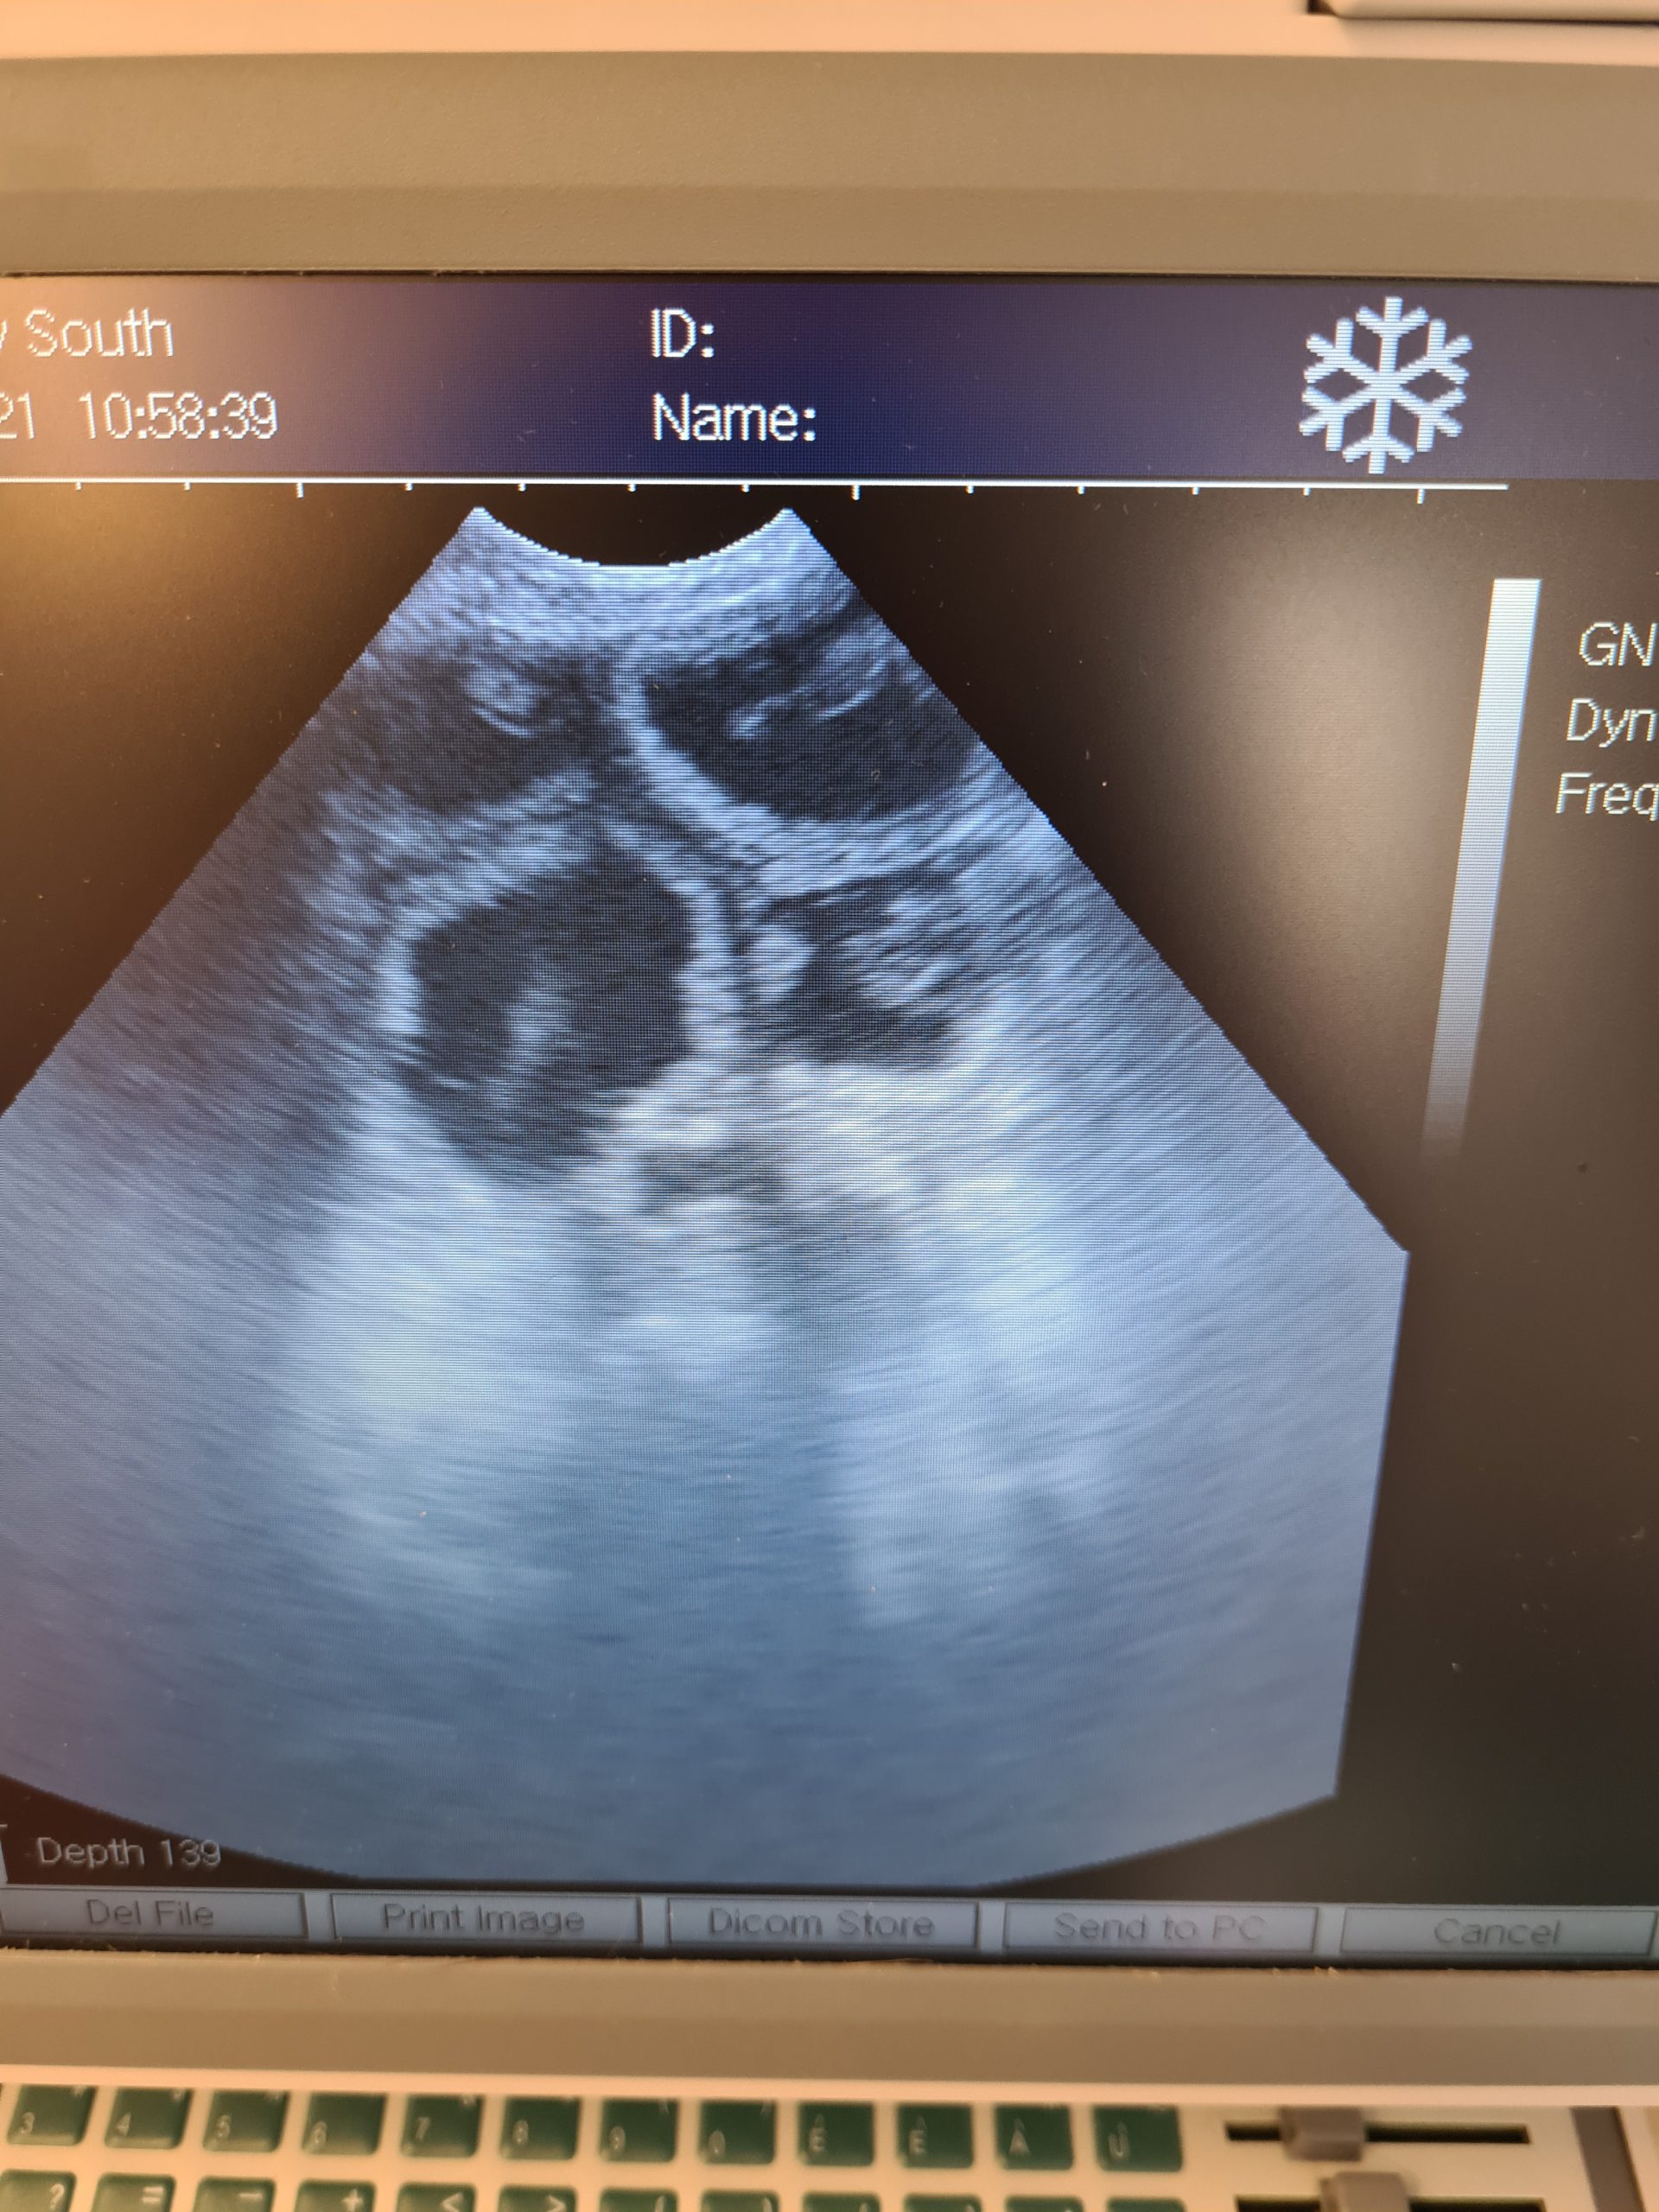

Daschund and Maltese scans following cytology and a.i. here at the clinic

Day 30 we saw 6